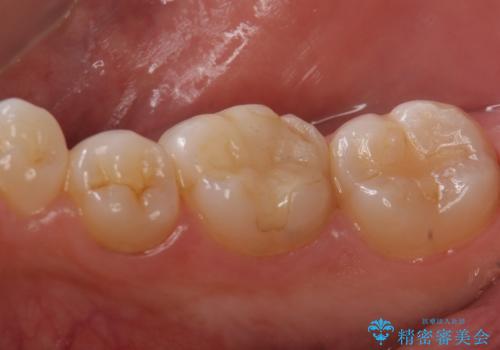

患者と相談し、金属よりも白いものを入れたい、また、もう歯が欠けてやり直すのは嫌だとのご希望だった。

そのため、歯質の削除量は増えるが、クラウンで被せる③の方針で行くことになった。

多少大きく削ることになりましたが希望に沿った処置となり、満足して頂けました。